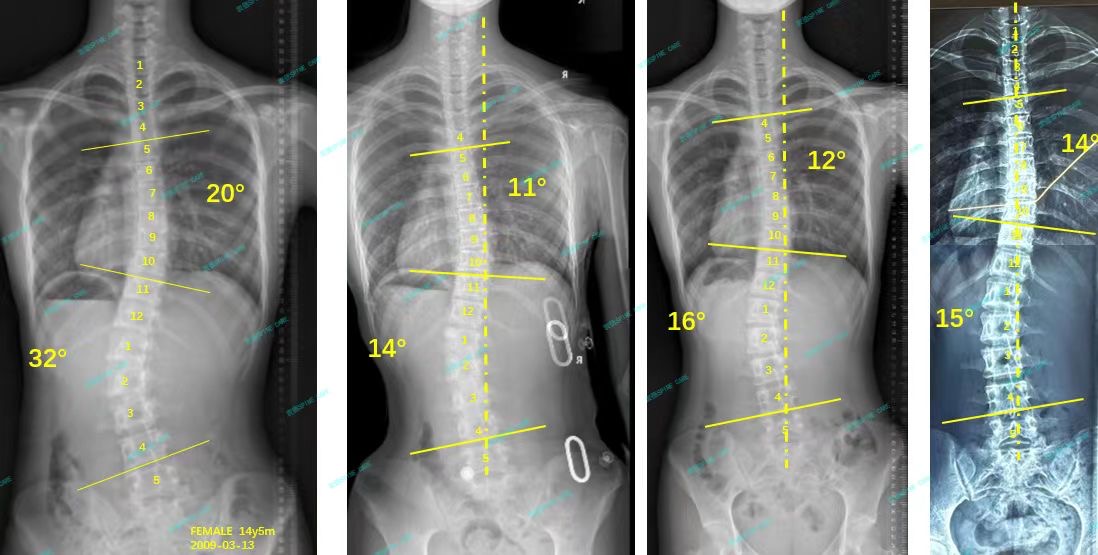

案例主人:苗苗 发现侧弯年龄:16岁 侧弯情况:Cobb角测32°

你好,我叫苗苗,胸弯20度,腰弯32度。妈妈很早就发现了我有脊柱侧弯,于是从网上找了一家私立机构带我每天去做训练,做了半年多,但是没有任何好转,于是来到了衷德脊柱。

Hello, my name is Miaomiao, with a chest bend of 20 degrees and a waist bend of 32 degrees. My mother discovered that I had scoliosis very early, so she found a private institution on the Internet to take me to do daily training. I did it for more than half a year, but there was no improvement, so I came to Zhongde Scoliosis Clinic and Research Center.

杨博士看了我的x片并且评估了我的体态之后,建议我做ZDT矫正训练+佩戴支具,我和妈妈在杨博士的专业下决定试试。一开始戴支具拍片的效果很好,我也每周都坚持来衷德脊柱做训练,每天也都坚持戴支具,后来脱支拍的x片显示我的度数已经降低了一半了!这样让我也更有动力继续坚持训练。

After Dr. Yang looked at my x-ray and evaluated my posture, he suggested that I do ZDT corrective training + wear brace. My mother and I decided to try it under Dr. Yang's major. At first, the results of taking x-ray with braces were very good. I also insisted on coming to Zhongde for spinal training every week and wearing braces every day. Later, the x-ray taken with braces showed that my degree had dropped by half! This also gives me more motivation to continue training.

来到衷德不知不觉两年多了,我和妈妈都十分信赖杨博士和所有康复师,最近脱支后拍x片显示我的胸弯从20度降到了14度,腰弯从32度降到了15度,我很开心!

It has been more than two years since I came to Zhongde without realizing it. My mother and I trust Dr. Yang and all rehabilitation therapists very much. Recently, an x-ray without wearing brace showed that my chest bend dropped from 20 degrees to 14 degrees, and my waist bend dropped from 32 degrees to 15 degrees, I am very happy!